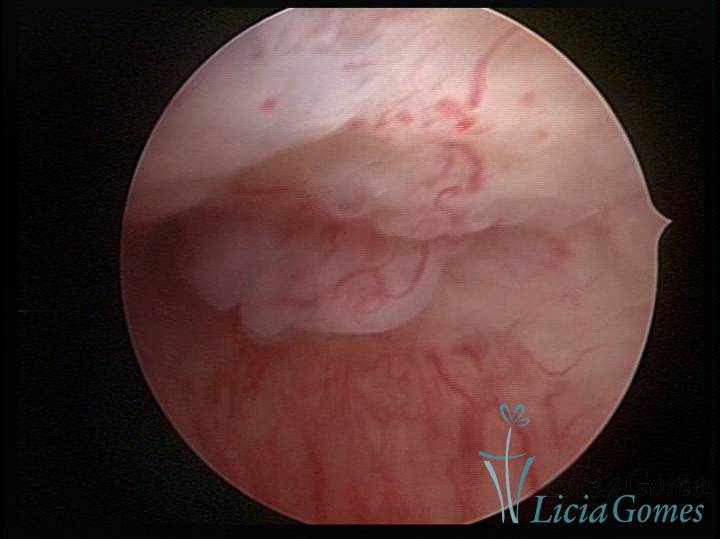

Este pode apresentar uma gama variável de aspectos macroscópicos, com aspecto pseudopolipoide; lembrando tecido cerebroide ou com reação deciduoide;a vascularização superficial é mais evidente e com vasos em formatos de saca-rolha ou espirais visualizando também a vascularização com atípias, com aumento do calibre dos vasos superficiais, pode ser encontrado também tecido em necrose, poderá haver um pequenos dendritos (papilomatoso).